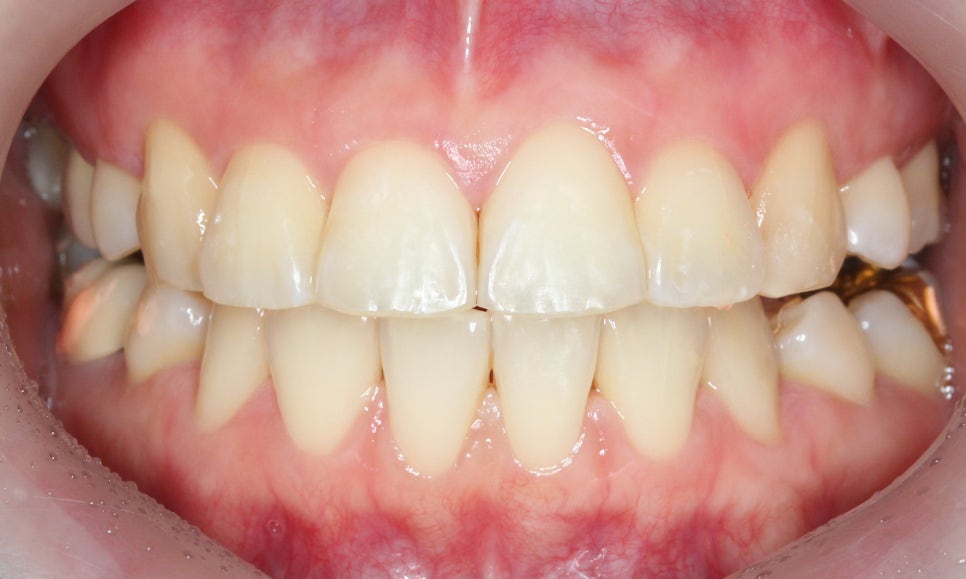

대치동치과 돌출입 교정 전 모습입니다.

전치부의 치아 배열을 보면

앞니가 튀어나와 있고 상하악의

정중선이 변위된 모습을 확인할 수 있는데요,

치아의 중심이 잘 맞지 않는 경우

어금니 부분이 어긋나게 교합되거나

턱 부분의 교합이 좋지 않은 상황일 수 있습니다.